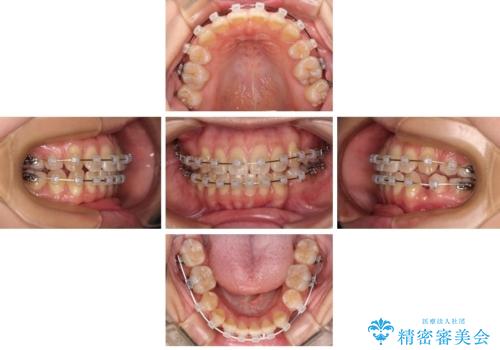

非接触の前歯と下顎のデコボコ ワイヤー装置による矯正治療

- クリアブラケット

- 上下顎前歯部の非接触(開咬)と下顎のデコボコを主訴に来院された患者様です。

右側上下と左上の小臼歯が一本ずつ少なく、さらに骨格的な左右差もあり上下の真ん中の位置がずれています。

下顎のデコボコの解消と、真ん中の位置を改善するために左下の小臼歯を抜歯することとしました。

また、開咬を改善するため臼歯部にアンカースクリューを用いて圧下する力をかけていきました。

舌を突出する癖があり、それにより開咬が悪化したり、後戻りの原因になるため、舌のトレーニング(MFT)も行いました。